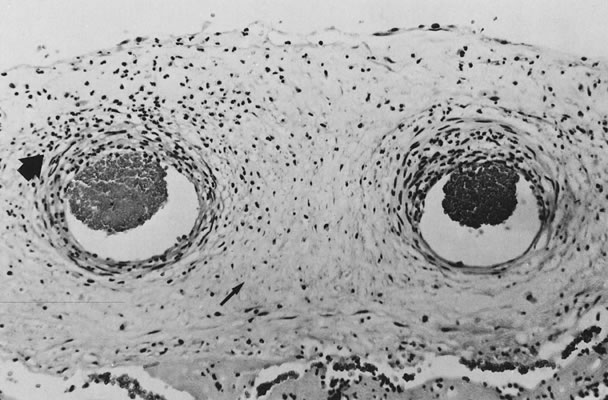

The infectious agent may colonize the extraplacental membranes or may cross intact or ruptured membranes into the amniotic fluid. If there is decidual or choriodecidual colonization, neutrophils are recruited from the decidual vasculature (by chemotactic cytokine stimuli generated locally). These cells may stay local to the chorion and decidua (rather than migrating out of these tissues toward the amnion/amniotic fluid space). In this pattern of inflammation, termed necrotizing,2 tissue destruction and neutrophil infiltration of the decidua and chorion predominate, with pockets of neutrophil debris studding the residual decidua. On the other hand, bacteria or their toxins may enter the amniotic fluid proper. Then, intra-amniotic cytokines call neutrophils out of the decidua, across the chorion, and into the amnion, often leaving the decidua and chorion well preserved, with little nuclear debris or damage. The fetus also responds with recruitment of inflammatory cells out of the fetal blood flow (Fig. 2).2 “Marginating” inflammation predominates if amniotic fluid colonization is an early part of the infectious process (Fig. 3). A combined pattern of both destructive or necrotizing deciduitis and a margination toward the amnion can be seen when amniotic fluid inflammation occurs comparatively later in the infectious process. Bacteria or their toxins in the amniotic fluid elicit maternal neutrophil margination first in the subchorionic space. Recruited neutrophils then migrate across the chorion and amnion into the amniotic fluid (Fig. 4). Microscopic examination should include samples from the zone of spontaneous rupture of the membranes, the pericervical membranes being the area first affected when infectious agents ascend across the cervix. The extraplacental membranes distant from the site of rupture (often a membrane roll), sections of umbilical cord, and the chorionic plate are required to provide clues to the following questions: Did bacteria gain access to the amniotic fluid space? Did the fetus respond to the infectious process? It is this fetal response that may be critical to serious long-term sequelae, especially those related to prematurity, including lung disease3 and brain damage.4,5,6,7

Fig. 2. Unidirectional response of inflammatory cells from chorion toward infected amniotic cavity (hematoxylin and eosin, ×100). Chorionitis (maternal inflammatory response, arrow) and chorionic vasculitis (fetal inflammatory response, arrowhead ).